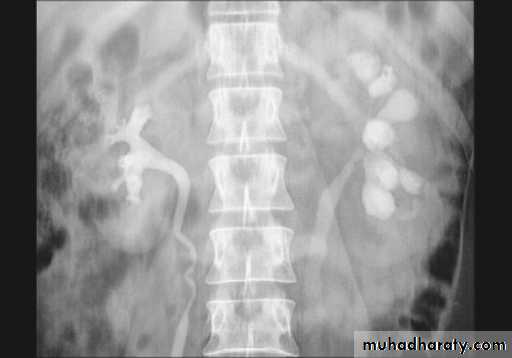

3. After 10 minutes with compression, to get better distention of the pelvis and calyces.

Urinary tract